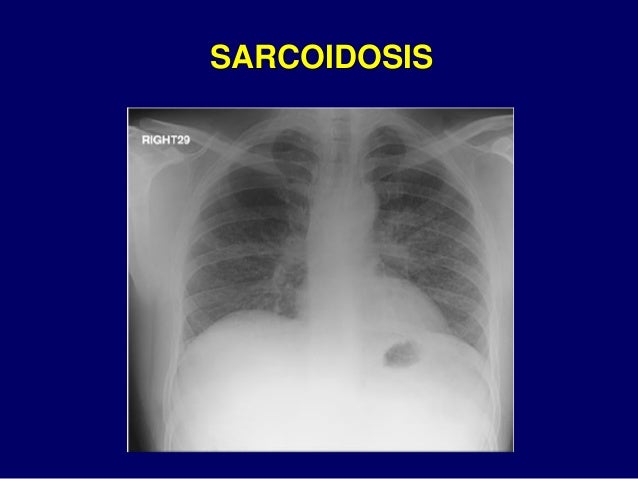

108. 108. 5. CÁC TỔN THƯƠNG KHÁC HẠCH LYMPHO LỚN

125. 125. NGUYÊN NHÂN XƠ PHỔI Thùy trên Thùy giữa Thùy dưới  Lao  Viêm phế nang dị ứng ngoại sinh mạn tính  Xạ trị  Viêm cột sống cứng khớp  Xơ phổi lớn tiến triển tự miễn  Nhiễm Histoplasmosis  Sarcoidosis  Viêm phổi mô kẽ không do tác nhân vi sinh vật  Xơ phổi do tiếp xúc Asbestos  Xơ phổi do thuốc (thường gặp nhất)

131. 131. SARCOIDOSIS